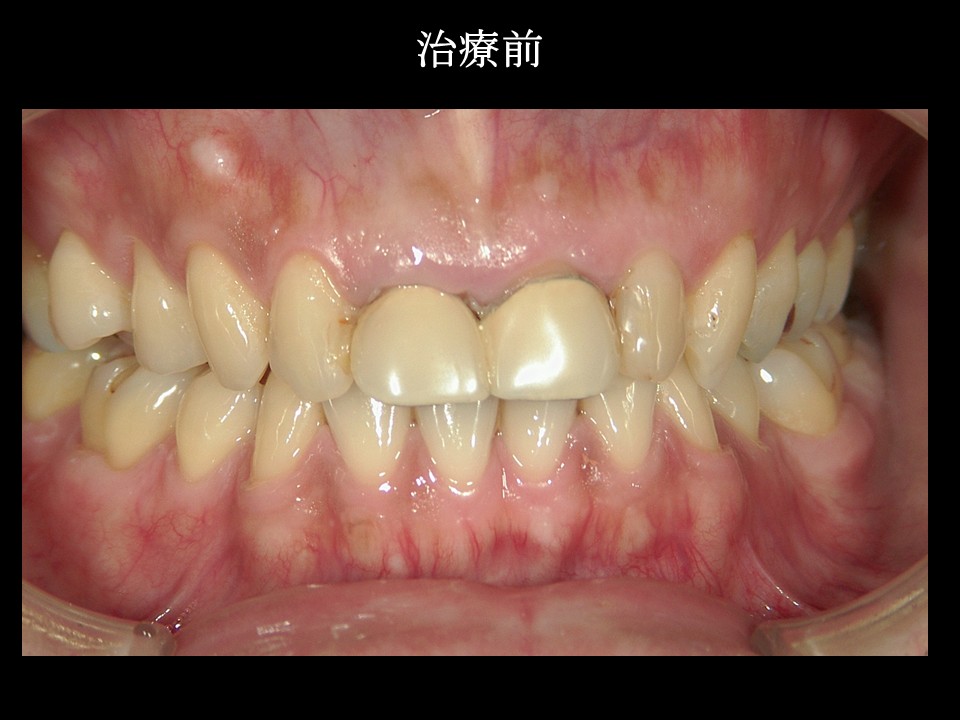

今回はの患者様は40代男性。

「20年前に時保険診療でいれた差し歯の周りから血が出るし、なんか重い痛みがたまにある」

というお悩みでした。

当時は仕事が忙しく、急いで治療してもらったそうなのですが、差し歯のまわりの歯ぐきは炎症によりうっ血して黒ずみ、レントゲン上では歯の根に膿がたまっている状態でした。